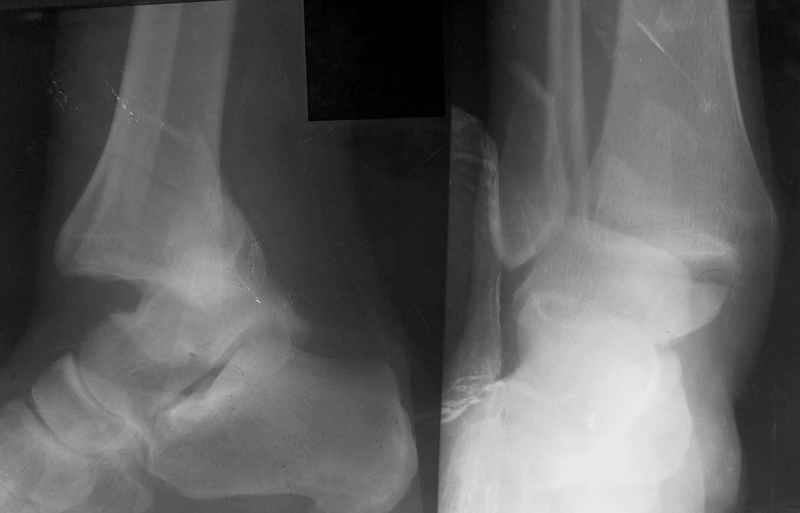

Re: Открытый переломо-вывих стопы.

Заднепровский Никита 20 Апрель 2006, 21:37

Здравствуйте, Алексей.

Прооперировал на следующий день после того как увидел эту больную и взял ее на курацию. Почему не прооперировали другие? Вопрос не ко мне ...

Стабильность г\ст сустава обеспечивается во-первых наружной лодыжкой (ключ), во-вторых задним краем б\б кости, в-третьих связками синдесмоза и межкостной мемраной, только в-четвертых медиальной лодыжкой (дельтовидной связкой. Это классика! А пяточной кости и плюсневых костей здесь нет! зачем их фиксировать? см. вложенный файл.